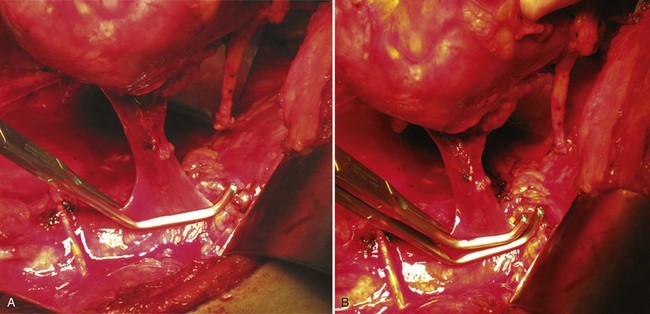

Transesophageal echocardiography is performed before making the incision to evaluate the cephalad extent of tumor thrombus (Fig. 54–102). Radical nephrectomy with removal of a perirenal or infrahepatic IVC thrombus is best approached through a chevron incision. For very large tumors involving the upper pole of the kidney a thoracoabdominal incision may be used instead. Most often these lesions are resected without CPB.

Figure 54–102 A and B, Technique for removing infrahepatic tumor thrombus with assistance of Rummel tourniquets avoiding cardiopulmonary bypass. Ao, aorta; IVC, inferior vena cava; RT. V, right vein.

(© The Lahey Clinic.)

The colon is reflected medially, and a Kocher maneuver is employed to mobilize the duodenum. A Bookwalter retractor is used for exposure. The caudate lobe of the liver can be exposed and a sweetheart retractor placed under it, taking caution to identify and safeguard the porta hepatis. Control of the IVC is obtained with limited manipulation to prevent embolization of tumor thrombus. Rummel tourniquets are placed above and below the thrombus and around the contralateral renal vein (see Figs. 54-103 and 54-104 on the Expert Consult website

). The renal artery, associated lumbar and minor hepatic veins, as well as the contralateral renal vein are isolated and circumferentially dissected. One can sacrifice perforating veins to the caudate lobe of the liver, which permits the IVC to be separated from the caudate lobe and exposes several more centimeters of IVC (Novick, 2007).

The renal artery and the ureter are ligated and divided. The specimen is mobilized outside the Gerota fascia, leaving the renal vein as the sole attachment. Preoperative renal angioinfarction may produce an inflammatory response that precludes safe early mobilization of the renal artery. In this instance the authors defer ligation of the renal artery until the tumor thrombectomy has been completed.

Venous occlusion is obtained with the previously placed Rummel tourniquets. An alternative is to use a Satinsky clamp on the IVC and a bulldog vascular clamp on the contralateral renal vein (Novick, 2007). A longitudinal anterior cavotomy is made, and the thrombus is freed from the caval wall to the level of the renal vein ostium using a spatula and gentle manipulation. In most cases the thrombus is not attached to the wall of the cava. The IVC is gently flushed with heparinized saline and evaluated for residual fragments. The infrarenal clamp is released transiently to purge the system of debris and limit the risk of embolus. Alternatively the suprarenal clamp can be released while applying positive pulmonary pressure to flush the cava free of fragments. The cavotomy is closed with a continuous 4-0 polypropylene suture (Figs. 54-105 and 54-106 on the Expert Consult website

). Radical nephrectomy is carried out after closure of the vena cava has been completed.